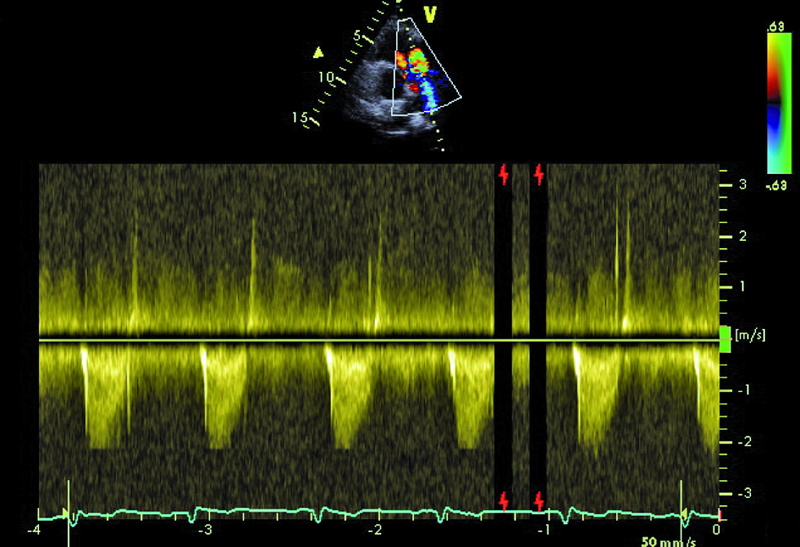

W badaniu echokardiograficznym zwrócono uwagę na powiększenie jamy lewej komory z nieznacznie upośledzoną kurczliwością mięśnia (ryc. 1). Stwierdzono także trójpłatkową zastawkę aortalną (ryc. 2) ze śladową niedomykalnością oraz małą niedomykalność mitralną. Te nieprawidłowości nie mogły tłumaczyć szmeru ciągłego w badaniu fizykalnym ani też nieznacznie powiększonej sylwetki serca. Przyczyną szmeru ciągłego jest najczęściej przetrwały przewód tętniczy Botalla, łączący aortę i pień płucny. Połączenia takiego jednak w miejscu typowym nie znaleziono. Rejestrowano u chorego prawidłową średnicę pnia płucnego (ryc. 3) oraz nieznacznie przyspieszoną prędkość wypływu płucnego (ryc. 4). Szmer ciągły nakazywał poszukiwać innych rzadkich połączeń między dużymi naczyniami. Jedną z nich jest okienko aortalno-płucne, czyli tzw. fenestracja aortalno-płucna, i tę wadę właśnie rozpoznano u chorego.

Okienko powstaje wskutek nieprawidłowego podziału embriologicznego przegrody dzielącej aortę wstępującą oraz pień płucny. Lokalizacja okienka w obrębie aorty wstępującej może być różna, zależnie od tego, która część wspólnej przegrody ulega w toku rozwoju embriologicznego uszkodzeniu – proksymalna czy dystalna w stosunku do zastawek półksiężycowatych. Do rozpoznania wady wystarczy zwykle badanie echokardiograficzne. Na poziomie zastawek powinno się rejestrować dwa niezależne pierścienie zastawek półksiężycowatych. Istnienie okienka może zwykle sugerować brak echa w ścianie między dużymi tętnicami. W tym jednak przypadku takiej cechy nie stwierdzono. Na możliwość okienka wskazywała turbulencja w badaniu kolorowego doplera w pobliżu pierścieni zastawki aortalnej i płucnej (ryc. 5, 6). W badaniu techniką kolorowego doplera rejestruje się przepływ o dużej prędkości, czasami wyraźnie ze strony lewej ku prawej lub przepływ dwukierunkowy. W różnicowaniu trzeba brać jednak pod uwagę inne nieprawidłowości, jak odejście prawej tętnicy płucnej od aorty wstępującej. Dawniej okienko aortalno-płucne operowano za pomocą łaty z dakronu bądź osierdziowej lub przy niewielkiej komunikacji za pomocą szwu. Obecnie, jeśli nie stwierdza się innych współistniejących nieprawidłowości, bierze się pod uwagę zamknięcie okienka za pomocą okludera i do tego rodzaju zabiegu chory został zakwalifikowany. Średnica okienka (4,5 mm) została ustalona w badaniu tomografii komputerowej.